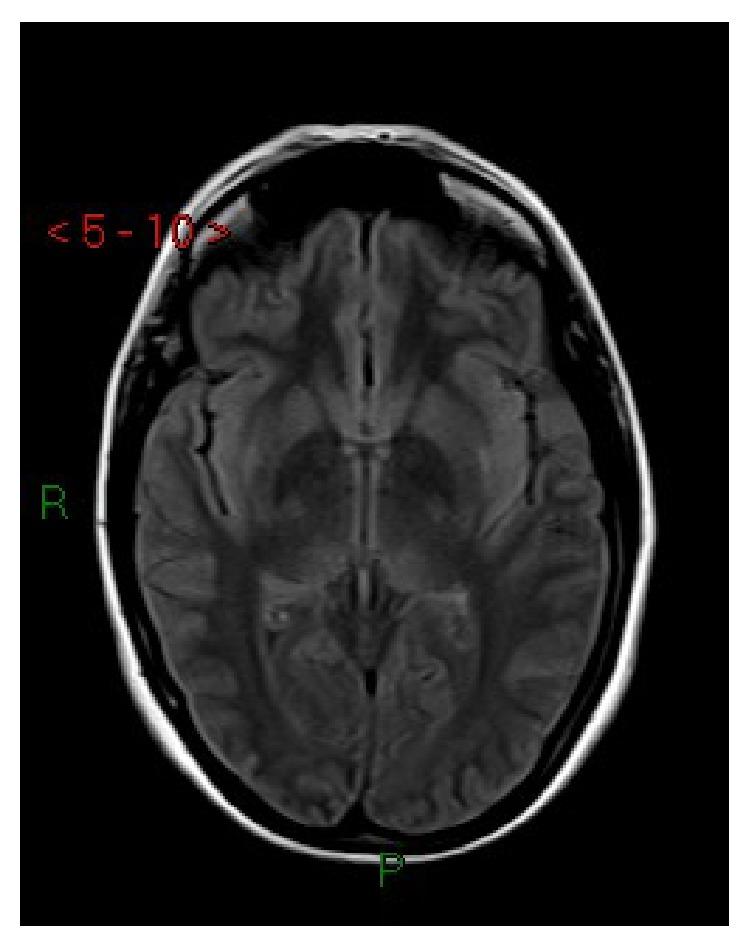

Posterior reversible encephalopathy syndrome (PRES) is a neurological syndrome associated with a number of conditions including preeclampsia. It is characterized by seizures, alteration of consciousness, visual disturbances, and symmetric white matter abnormalities, typically in the posterior parietooccipital regions of the cerebral hemispheres, at computed tomography (CT) and magnetic resonance (MRI). We report three new cases of PRES in preeclamptic patients and describe the management of these patients. We present a brief review of other cases in the literature, with particular attention to the anesthetic management.

后部可逆性脑病综合征(PRES)是一种与包括先兆子痫在内的多种病症相关的神经综合征。其特征为癫痫发作、意识改变、视觉障碍以及对称的白质异常,在计算机断层扫描(CT)和磁共振成像(MRI)上,这些异常通常出现在大脑半球的后顶枕叶区域。我们报告了3例先兆子痫患者发生PRES的新病例,并描述了这些患者的治疗情况。我们对文献中的其他病例进行了简要综述,尤其关注麻醉管理。